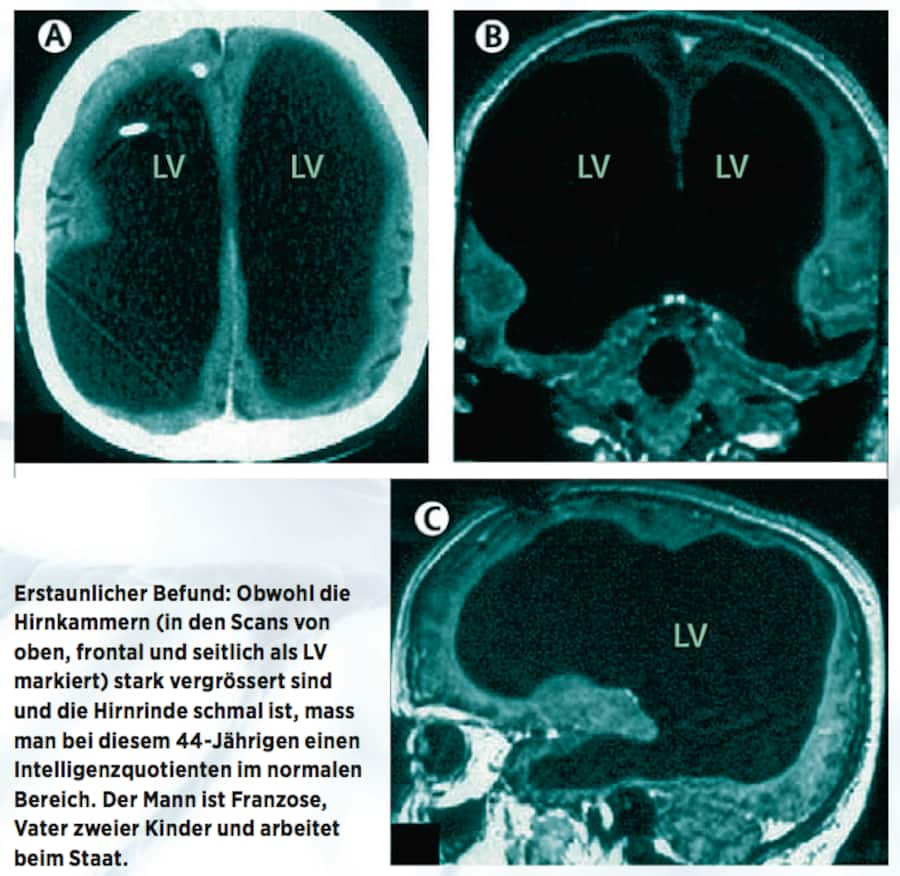

Lorber hat den Fall eines Mathematikstudenten beschrieben, der «einen Intelligenzquotienten von 126 hat, beste Noten in Mathematik schreibt und sozial völlig normal ist. Doch hat dieser Junge so gut wie kein Gehirn.» In der Hirnrinde fand sich statt der üblichen 1,5 bis 5 Millimeter nur eine knapp 1 Millimeter dünne Schicht Nervenzellen. 95 Prozent des Schädelraums waren mit Hirnflüssigkeit gefüllt. «Ich kann nicht sagen, ob dieses Gehirn 50 oder 150 Gramm wiegt. Aber es ist klar, dass es bei weitem nicht in der Nähe der üblichen 1,5 Kilogramm liegt», befand Lorber.

Der Student war zu ihm geschickt worden, weil sein Kopf etwas grösser war als üblich. So wie es typisch ist bei einem Hydrozephalus, der Vergrösserung der mit Flüssigkeit gefüllten Kammern im Gehirn.

Nachzulesen ist der Fall im Wissenschaftsmagazin «Science», Jahrgang 1980. Schon der Titel des Artikels dürfte damals die Leserschaft überrascht haben: «Ist Ihr Gehirn wirklich notwendig?» Lorber hatte über 600 Fälle von Hydrozephalus untersucht und kam zur Erkenntnis, dass «einige Patienten viel normaler sind, als sich aus ihren Hirnscans ableiten liesse».

Mit Blick auf den Mathestudenten wird im «Science»-Artikel auch gleich die entscheidende Frage gestellt: «Wie kann sich jemand mit einer grotesk verringerten grauen Substanz nicht nur ohne soziale Defizite zwischen seinen Kollegen bewegen, sondern sogar noch hohe akademische Leistungen erbringen?»